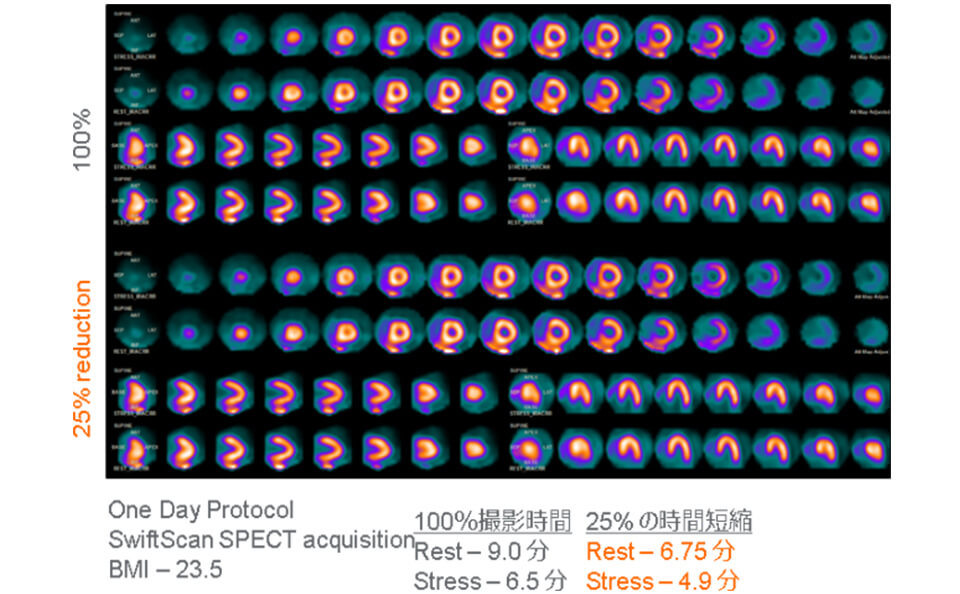

核医学検査部⾨

核医学検査とは、放射性同位元素(Radio Isotope)を⽤いて⾏う検査です。体内にRIを含む薬剤を投与(経⼝もしくは静脈注射)する事で、全⾝へと運ばれ、特定の臓器や組織に取り込まれて集積します。

これを特殊な撮像装置(ガンマカメラ)を利⽤して、放出される放射線(主にガンマ線)を検出することで臓器や組織の形状・機能を調べます。

注射後、⽬的の臓器や組織に薬剤が集積するまで約3時間を要する検査や数⽇かかる検査もあります。検査は装置のベッド上で安静状態の寝た体勢で⾏います。撮影時間は30分〜1時間程度です。

検査に⽤いる放射性医薬剤は⼈⼯的に作られたもので、副作⽤はほとんどありません。体内に⼊った薬剤からは放射線が出ますが極微量で、検査を受ける本⼈や周囲の⼈々への影響について⼼配はありません。検査も苦痛なく⾏えるのが特徴です。

核医学検査に⽤いる薬剤のほとんどは尿・便排泄されます。また、放射線の量は時間とともに減少していくので、後々まで体内に残って放射線が出ることはありません。

ガンマカメラ(GEヘルスケア NM830)

ガンマカメラ(GEヘルスケア NM830)

当センターでは、主に⾻シンチグラフィ、⼼筋(負荷・安静)シンチグラフィ、脳⾎流シンチグラフィの検査を⾏っています。そのほかにも、甲状腺シンチグラフィや腎動態シンチグラフィなど多種多様な検査の受け⼊れ態勢も整っています。

-

⾻シンチグラフィ

⾻シンチグラフィ

-

⼼筋シンチグラフィ

⼼筋シンチグラフィ